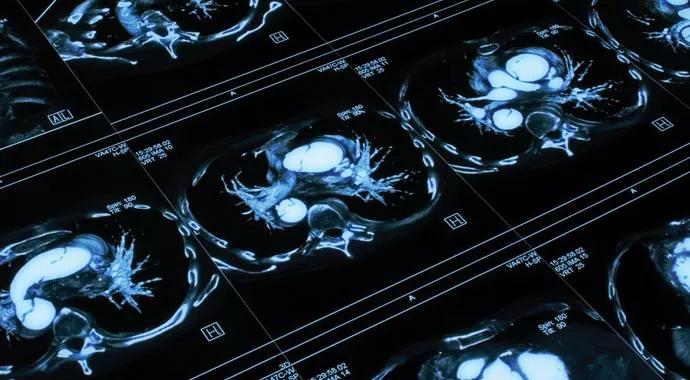

The PETAL Network was formed to develop and test, through clinical trials, new methods to prevent, diagnose and treat Acute Respiratory Distress Syndrome (ARDS), especially at an early stage in disease progression. It emphasizes a teamwork approach, enabling clinicians from many medical areas to work together on research projects.

As its title suggests, PETAL will shift some of its ARDS research to focus on earlier aspects in disease progression, including (a) recognition and treatment of patients within the first several hours of the onset of ARDS and (b) recognition and utilization of preventive approaches in patients with conditions that predispose to ARDS. This new approach has been long-considered, but the creation of PETAL is the first strong indication of its national priority to NHLBI.